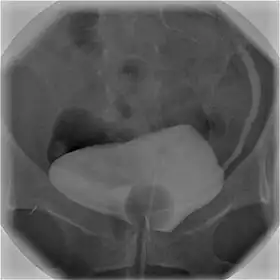

![]() Cystography image showing contrast in the urinary bladder and left ureter (right side of image). | |

In radiology and urology, a cystography (also known as cystogram) is a procedure used to visualise the urinary bladder.

Using a urinary catheter, radiocontrast is instilled in the bladder, and X-ray imaging is performed. Cystography can be used to evaluate bladder cancer, vesicoureteral reflux, bladder polyps, and hydronephrosis. It requires less radiation than pelvic CT, although it is less sensitive and specific than MRI or CT. In adult cases, the patient is typically instructed to void three times, after which a post voiding image is obtained to see how much urine is left within the bladder (residual urine), which is useful to evaluate bladder contraction dysfunction. A final radiograph of the kidneys after the procedure is finished is performed to evaluate for occult vesicoureteral reflux that was not seen during the procedure itself.[1]